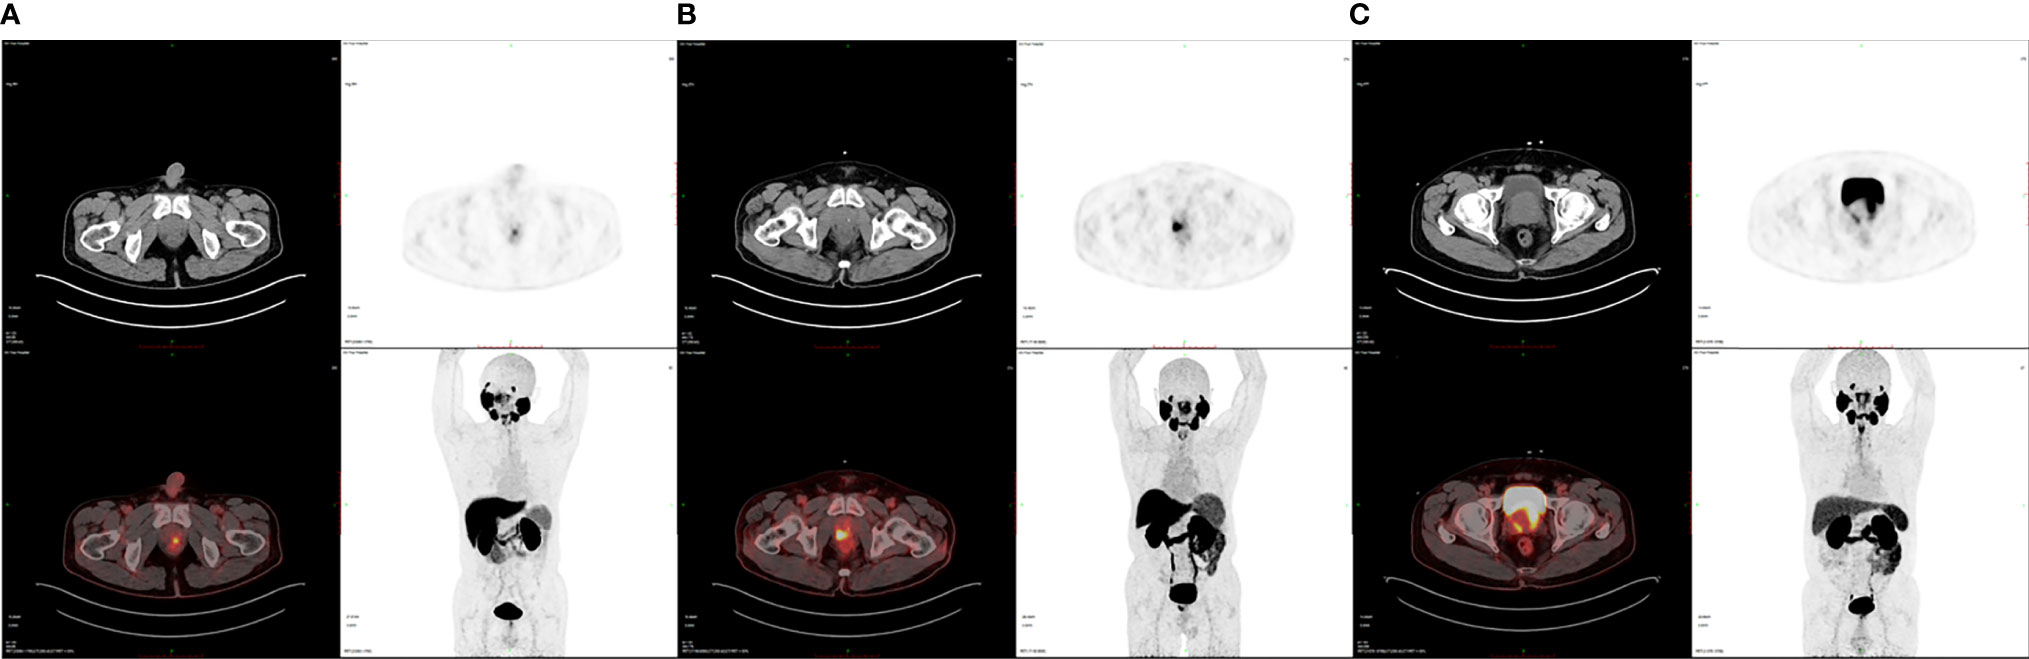

Finally, we enrolled 62 patients newly diagnosed as PCa for 18F-DCFPyL PET/CT examination in our institution without previous local or systemic therapy. Among them, 18 patients were at low risk, 12 at intermediate risk, and 32 at high risk of PCa based on the D’Amico scale. The demographic and clinical data of patients are shown in Table 1. No statistical significance was observed in PCa patients of different risks in terms of age, BMI, and diabetes as well as hypertension history (P > 0.05), demonstrating comparability of these clinical data among the groups. Table 2 shows the intraprostatic PSMA uptake of 18F-DCFPyL PET/CT in different risk groups. Significantly decreased levels of SUVmax, SUVmean, TL-PSMA, and P/M ratio were observed in the low- or intermediate-risk groups or both, compared with the high-risk group. However, only P/M ratio significantly elevated in patients with intermediate risk [mean ± SD (median): 46.58 ± 9.74 (45.27), P = 0.042] or high risk [98.95 ± 38.83 (97.52), P < 0.001], compared with low-risk patients [12.33 ± 5.93 (9.81)]. Therefore, the P/M ratio has the possibility to become a diagnostic uptake parameter to discriminate among patients with newly diagnosed PCa at low, intermediate, and high risks. Figure 1 reveals the SUVmax, SUVmean, PSMA-TV, TL-PSMA, and P/M ratio of PCa patients. What stands out in this figure is the significant difference in the P/M ratio between patients at low risk and patients at intermediate risk. Figure 2 shows the representative images of 18F-DCFPyL PET/CT of PCa patients at different risks, and SUVmax and P/M ratio increased obviously with increasing risk. No statistical difference was exhibited among PCa patients at low, intermediate, and high risks in terms of PSMA-TV.

FIGURE 2

Figure 2 Representative 18F-DCFPyL PET/CT images of PCa patients at various risks. (A) SUVmax is 4.04 and the P/M ratio is 10.12 in a low-risk PCa patient. (B) SUVmax is 10.61 and the P/M ratio is 35.36 in an intermediate-risk PCa patient. (C) SUVmax is 30.94 and the P/M ratio is 91.26 in a high-risk PCa patient.